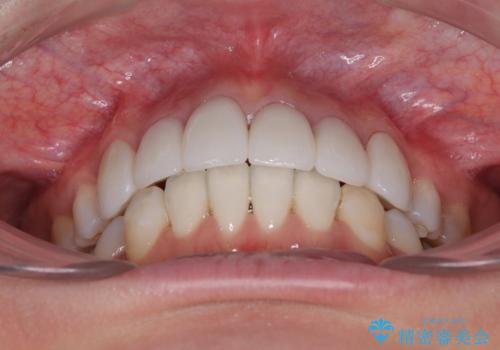

4本とも歯根部先端の骨が炎症により吸収していることがレントゲン写真から示唆されたため、矯正治療後に4本を再根管治療し、その後上顎6歯をオールセラミッククラウンにて補綴治療することとしました。

歯並びだけでなく、歯の色も明るくなり、すっきりとした口元の印象となりました。